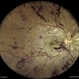

- ATYPICAL RETINITIS PIGMENTOSA, CRAO

- Fundus image of a 20 year old female who presented with bilateral visual loss since 2 months following history of typhoid fever, UTI, showing pale disc, sclerosed vessels,altered foveal reflex and granular fundus. Vision was light perception in both eyes. CBC, MRI Brain +Orbit , carotid doppler tests were WNL. Brucella IgG,IgM negative. ERG and VEP were abnormal.